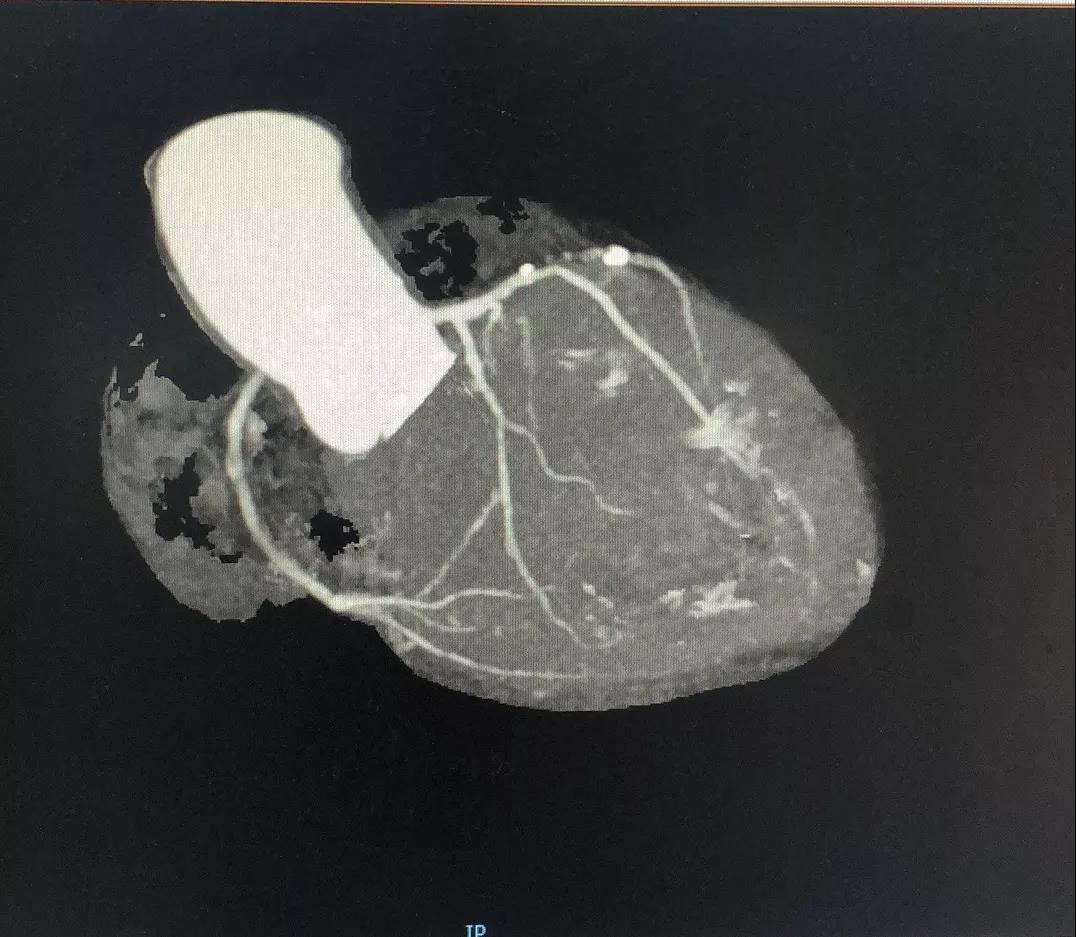

关于LAD

LAD CTA特点:

1、LAD发出第二对角支后即慢性闭塞;

2、闭塞入口不太清楚;

3、闭塞近段存在内膜钙化;

4、闭塞段血管的走行相对较直;

5、闭塞出口相对“健康”;

有了上述信息,再结合冠脉造影资料,开通LAD CTO就有了方案:

1、前向开通;

2、IVUS实时指导寻找闭塞入口;

3、XT系列导丝引导;

4、遇上阻力,升级Gaia或CP系列;

5、平行导丝技术;

6、ADR;

7、IVUS评估和优化支架植入。